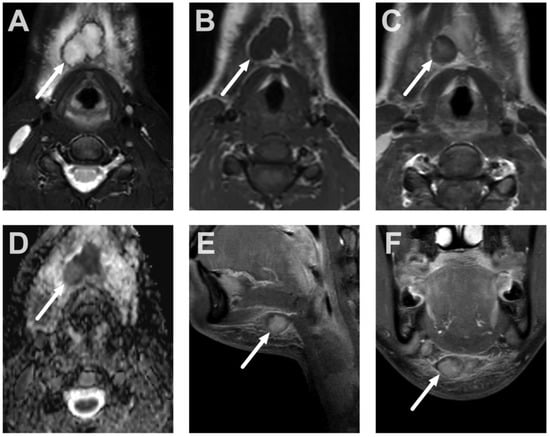

4.3. Oral Cavity

4.4. Sialadenitis

5.1. Lymphadenitis with Purulence vs. Necrosis

5.2. Cystic Masses